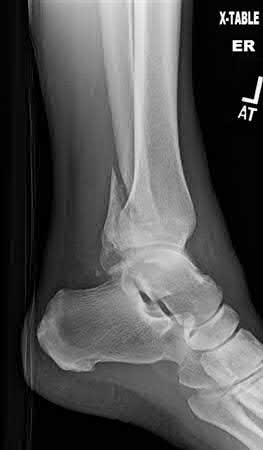

A 25-year-old male sustains an ankle fracture dislocation and undergoes open reduction and internal fixation. He returns to clinic five months following surgery complaining of continued ankle pain and instability with weight bearing. His immediate post-operative AP radiograph is seen in Figure A. Which of the following could have prevented this patient from developing persistent pain?

The patient presents with continued ankle pain and instability following open reduction and internal fixation. The radiograph in figure A demonstrates inadequate restoration of fibular length, likely leading to continued tibiotalar instability.